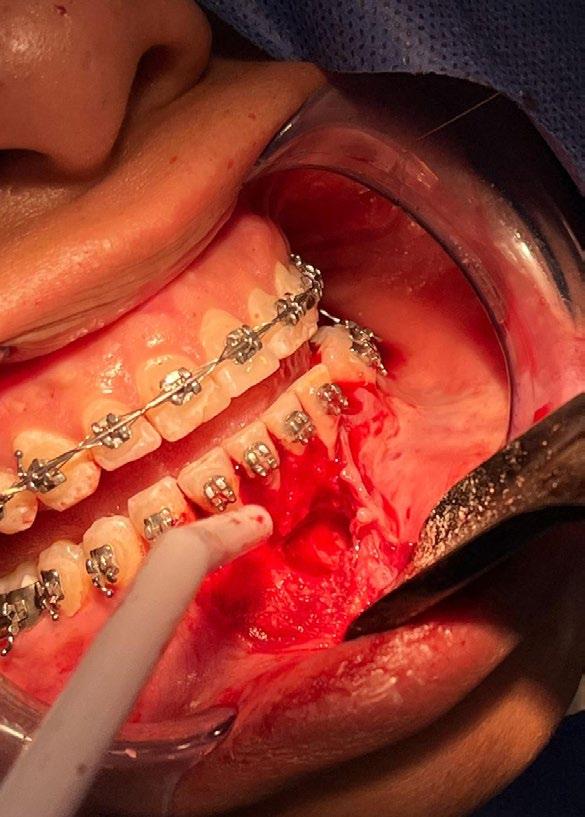

El tratamiento se realizó en las siguientes fases: la fase prequirúrgica incluyó la alineación, nivelación y la

extracción de los segundos premolares superiores e inferiores, con cierre de espacios. En la fase quirúrgica, se realizó una mentoplastia de avance e implantes en la zona malar. La fase postquirúrgica consistió en el detallado-retención. La aparatología utilizada fueron brackets de prescripción Roth .022 × .028; se colocaron bandas en los primeros molares superiores e inferiores, con tubos punteables en los O.D. 16, 26, 36 y 46, y tubos bondeables en el O.D. 27, además de un arco transpalatino y un arco lingual.

El tratamiento se realizó en las siguientes fases: la fase prequirúrgica incluyó la alineación, nivelación y la extracción de los segundos premolares superiores e inferiores, con cierre de espacios.

Previa asepsia y antisepsia, más colocación de campos en forma habitual, mediante infiltración troncular y de forma local, se realiza incisión

marginal con descarga lineal para levantar un colgajo seminewman (Figura 3). Se realiza ostectomía y osteotomía para liberar el órgano dentario retenido y facilitar su extracción (Figura 4). Una vez fuera de la cavidad bucal, se realiza tratamiento de conductos y obturación. De forma simultánea, se lleva a cabo la extracción atraumática del órgano dentario 73 (Figura 5) y la preparación alveolar del lecho receptor para recibir el órgano dentario a trasplantar bajo parámetros quirúrgicos (Figura 6).

Se enfatiza la mínima manipulación de los tercios radiculares del órgano dentario a trasplantar, intentando preservar, en lo posible, las fibras del ligamento periodontal. Se mantienen condiciones de hidratación a base de agua bidestilada durante su preparación, así como la sustitución neurovascular en su forma extrabucal. A nivel de los lechos receptores, se sigue un protocolo bacteriostático y bactericida no quelante.

En la zona postextracción del canino retenido (Figura 7), se realiza la conformación con materiales biocompatibles a base de xenoinjerto bovino y membrana de colágeno, para favorecer la correcta reparación de los tejidos blandos y duros, dadas las dimensiones del probable defecto, finalizando con sutura absorbible Vicryl 3-0 (Figuras 8 y 9).